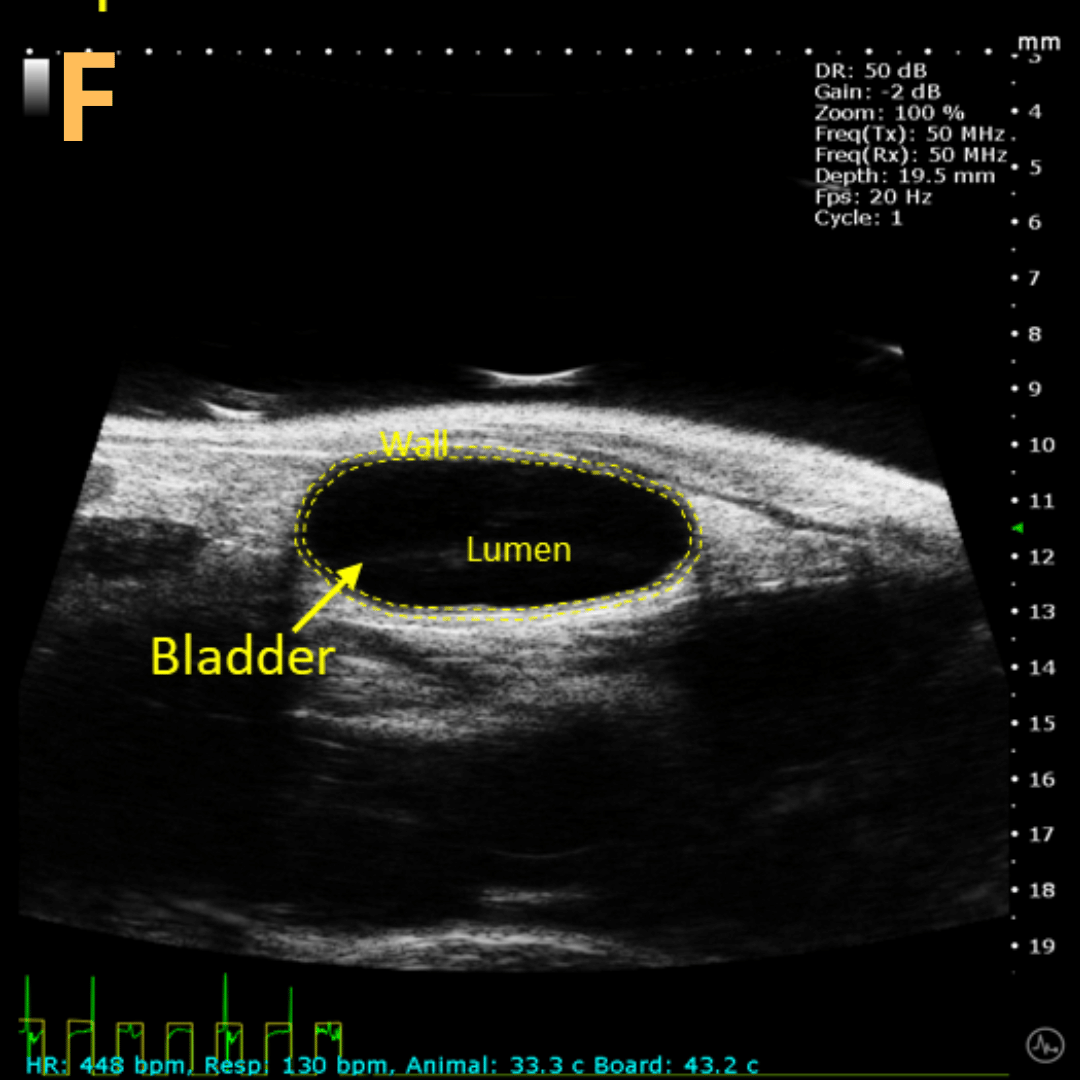

Basic Bladder Imaging

These are imaging from an emptied bladder (A – C) and a full bladder (D – F). This is A) a B-mode video scanning an emptied bladder with B) a still frame with C) the landmarks noted. This is D) a B-mode video scanning a full bladder with E) a still frame with F) the landmarks noted. Imaging on a wildtype C57B6J mouse model – acquired images are from Stephen Zderic’s lab at the Children’s Hospital of Philadelphia.